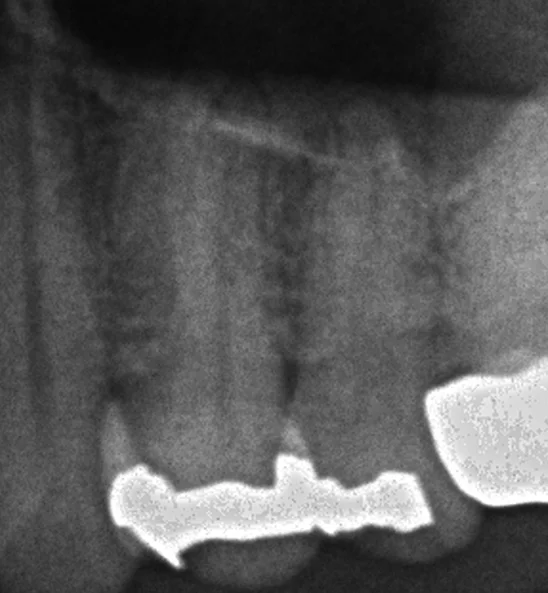

まずは診断の根拠となったレントゲンから

この画像で言うと、真ん中の歯なんですが・・・

金属の下が部分的にあからさまに黒くなっていますよね?

ここが虫歯になります。

後ろの金属については虫歯と断言しづらかったので、今回は介入してはいないです。